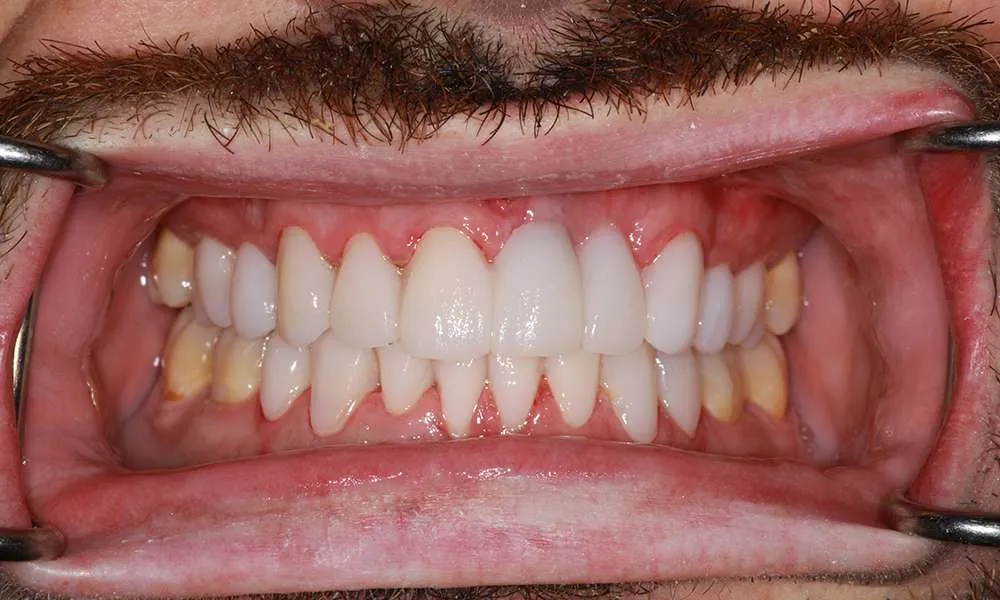

At Dr. Paul O'Malley's practice, we specialize in ultra-thin veneers that offer a minimally invasive solution for achieving a beautiful, natural-looking smile. Our approach focuses on providing aesthetic enhancements while ensuring the health and integrity of your natural teeth. These veneers are meticulously crafted from high-quality materials that closely mimic the appearance and texture of natural enamel. By utilizing advanced techniques, we ensure that the application process involves minimal alteration to your existing tooth structure. This method not only enhances the aesthetic appeal of your smile but also maintains the strength and health of your teeth, providing you with a durable and long-lasting solution.

Ultra-thin veneers are a type of cosmetic dental restoration made from high-quality, durable materials that expertly mimic the translucency and texture of natural enamel. These advanced veneers offer a revolutionary solution compared to traditional veneers, which often necessitate significant removal of tooth enamel. Designed to be as thin as a contact lens, ultra-thin veneers require minimal tooth alteration, thereby preserving more of your natural tooth structure. This innovative approach not only maintains the health and integrity of your teeth but also ensures a stronger and longer-lasting result. By choosing ultra-thin veneers, you benefit from a minimally invasive treatment that enhances your smile while supporting your overall oral health.